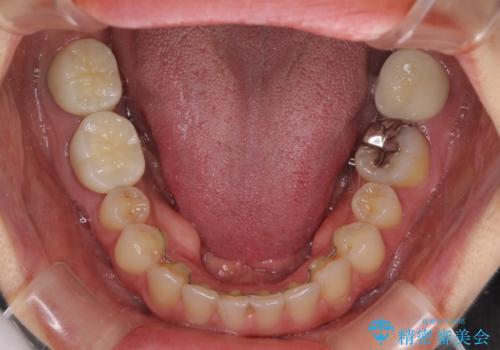

隙間だらけの歯列をきれいに インビザライン矯正とセラミック補綴治療

- 前歯の隙間と奥歯の目立つ銀歯を気にして来院された患者様です。

インビザラインにより下顎前歯の隙間を閉じるとともに、奥歯の咬み合わせを改善させることとしました。

矯正治療後には、銀歯のクラウンをセラミッククラウンへ替える補綴治療を行うこととしました。

左右奥歯の咬み合わせを変更させる必要があったため、治療期間は長くなることが予想されました。

1日22時間以上の装着時間をしっかりと守ってくださったので、順調に治療を進めることができました。